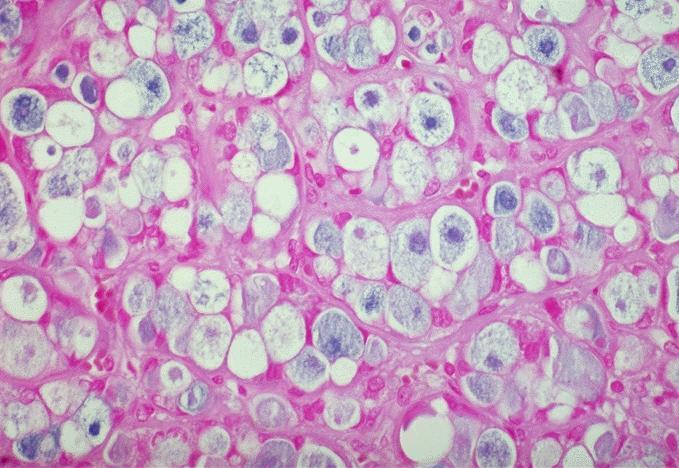

- Variants

- Hyperfunctioning adenoma (Plummer adenoma): tall columnar epithelium, papillary infoldings, vacuolated cytoplasm, watery colloid showing scalloping

- Clear cell follicular adenoma: follicular adenoma with clear cell change

Microscopic (histologic) images

Contributed by Shipra Agarwal, M.D., Andrey Bychkov, M.D., Ph.D., Mark R. Wick, M.D., Asmaa Gaber Abdou, M.D. and AFIP

Atypical adenomas: